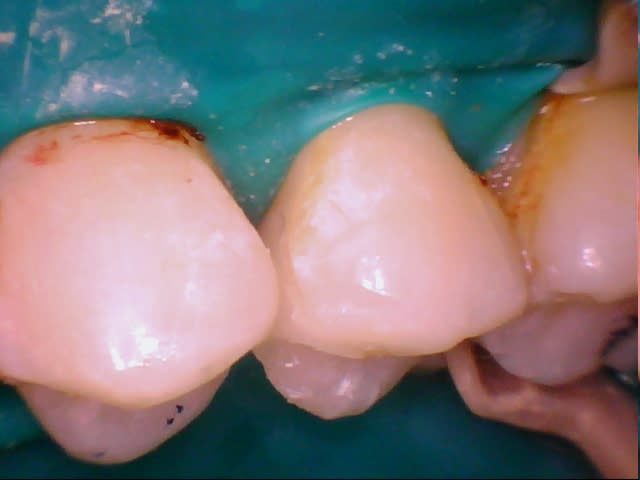

eMax de ce soir.

Collage automordançant G-Cem.

Bah voilà un argument de plus pour la levée de l'opposabilité pour les composites. Alors ameli? Qu'est qui favorise le plus l'accès au soins? Cet onaly qui doit coûter entre 300 et 500€ ou un compo à 150€ qui, collé dans les même conditions, aurait un pronostic équivalent?

Je trouve que c'est un patient qui devrait avoir des soins paro et des compo, pas des e-max. Et j'aime pas le collage au G-cem, en fait c'est le point faible de ton traitement, et c'est si facile de coller ce cas avec le total etch.

On peut penser qu'Arnaud aura vu le tartre sous-gingival et fait le nécessaire, mais pourquoi pas d'emax et plutôt des compos? Rapport à la taille des cavités? A l'hygiène pas top?

Oui rapport à la taille de la cavité. J'ai pas dit que c'était moins bien de faire un emax plutôt qu'un compo, je dis juste que c'est plus coûteux pour un bénéfice médical proche de zéro. Mais évidement si on veut faire un compo qui peut rivaliser avec cet onlay il faudra palper un pru plus que 28,92.

Il y a une équivalence thérapeutique entre les deux solutions tant que la forme de la préparation ne nécessite pas de délabrement, et bien que l'arsenal à mettre en œuvre est bien plus important pour l'inlay, je préfère de l'eMax dans ma bouche (et un peu de joint résine) qu'un compo.